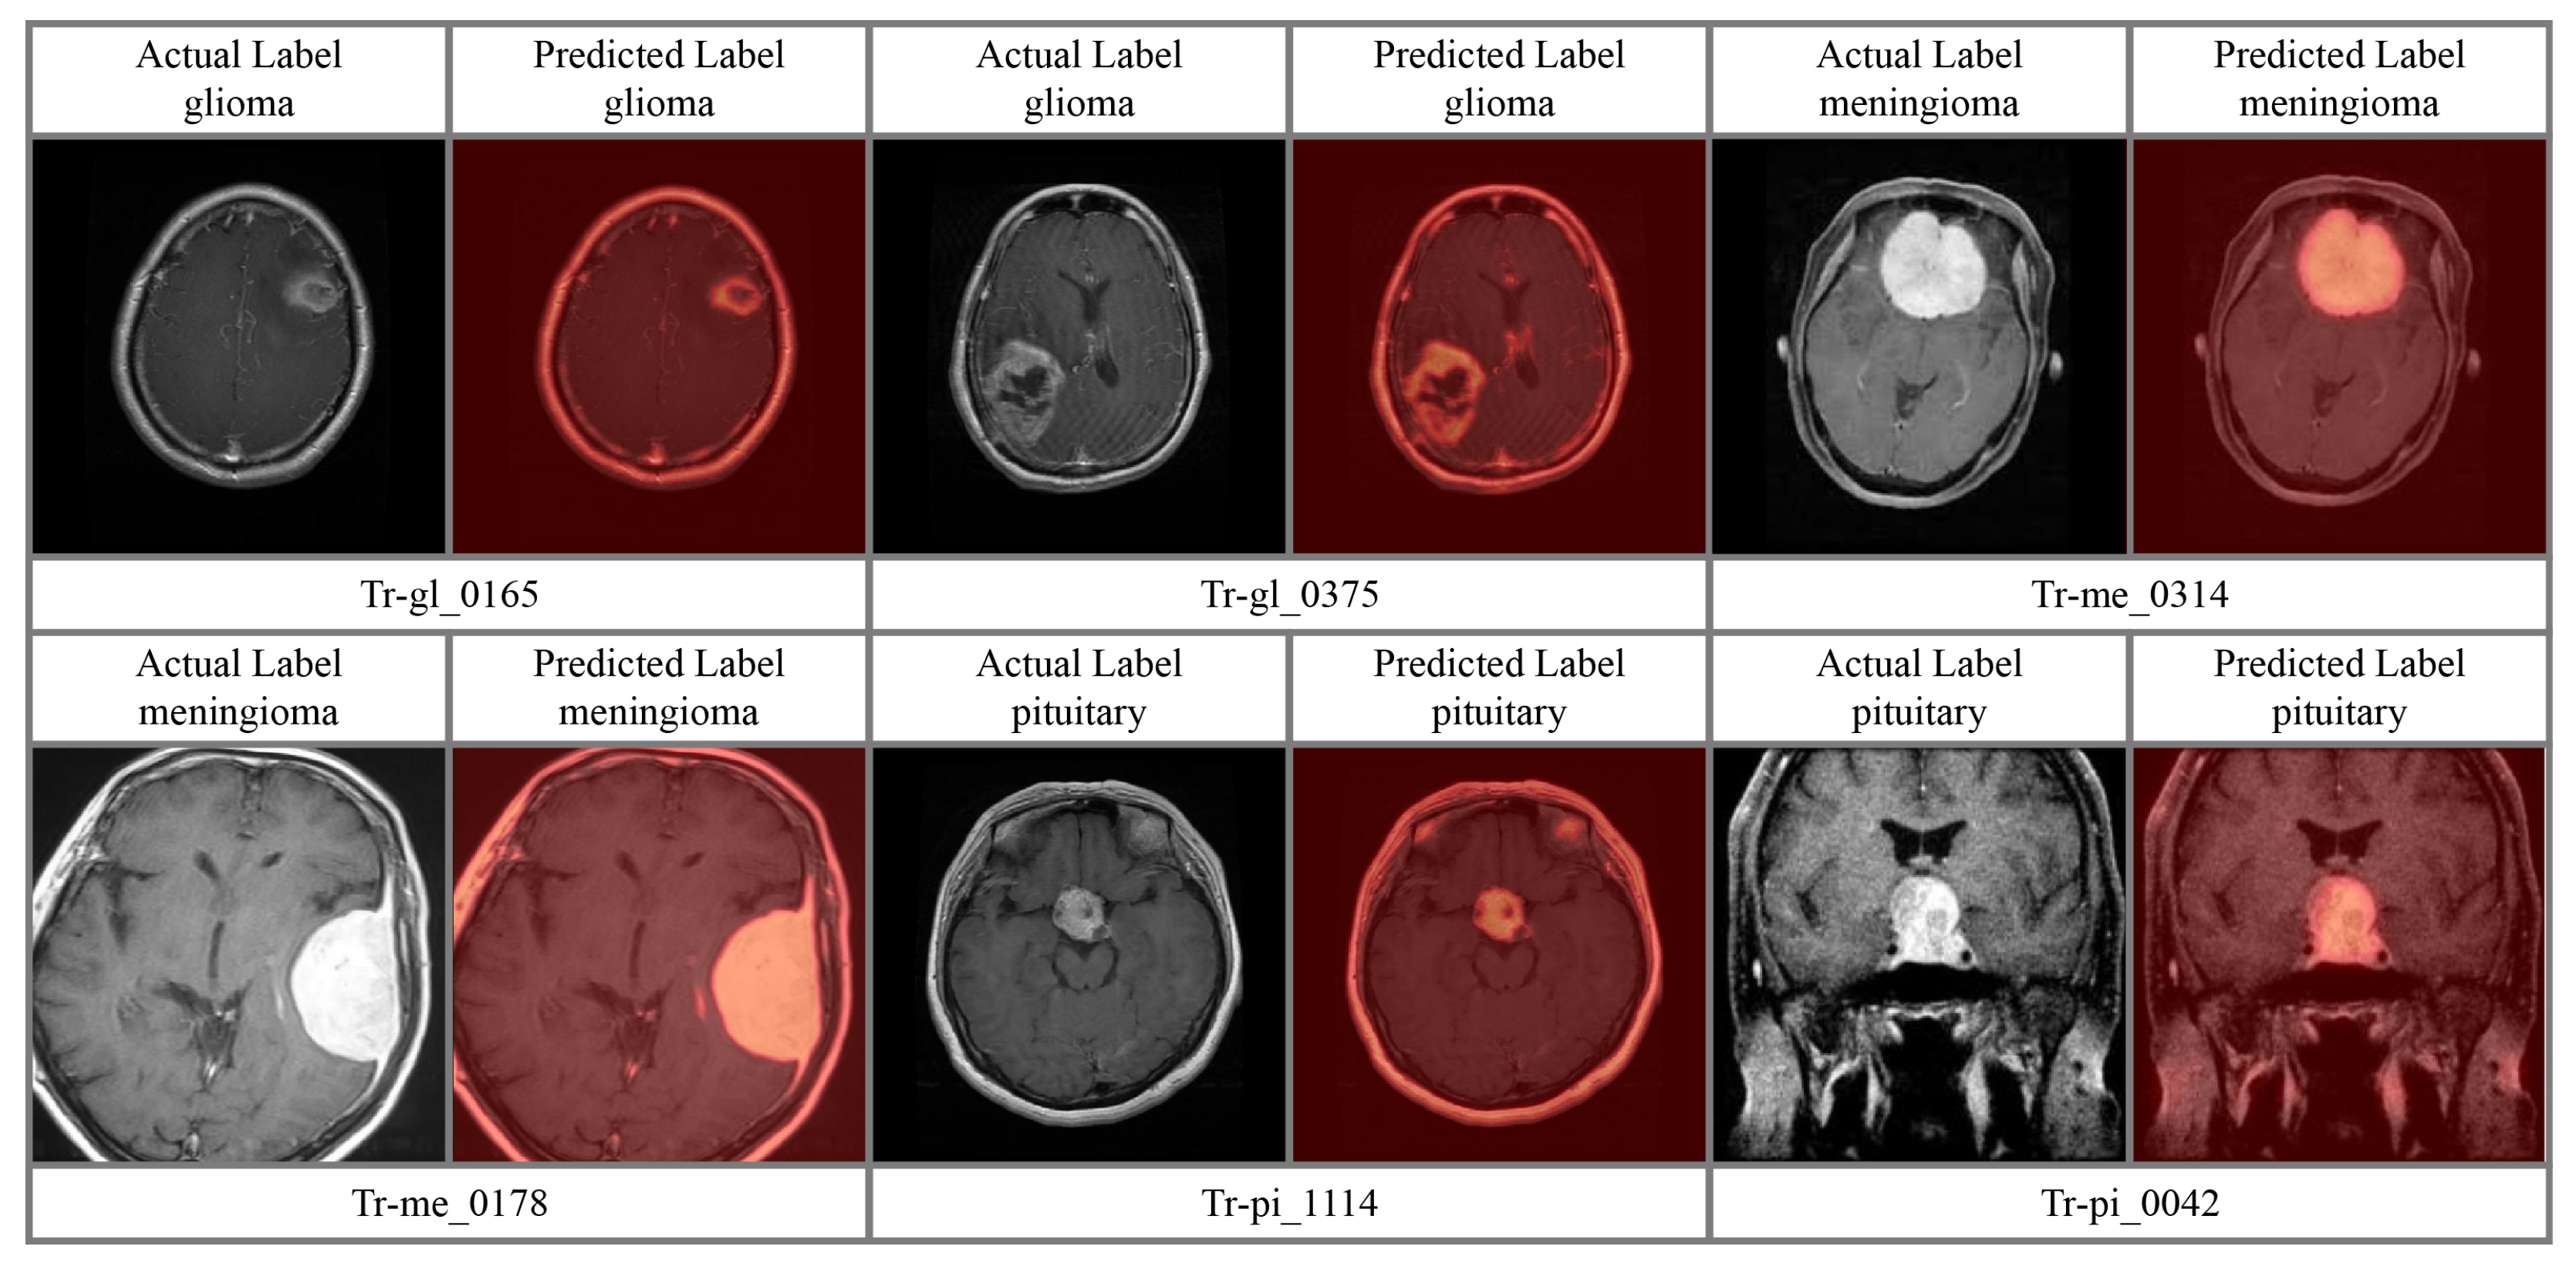

4.4. Attention Analysis